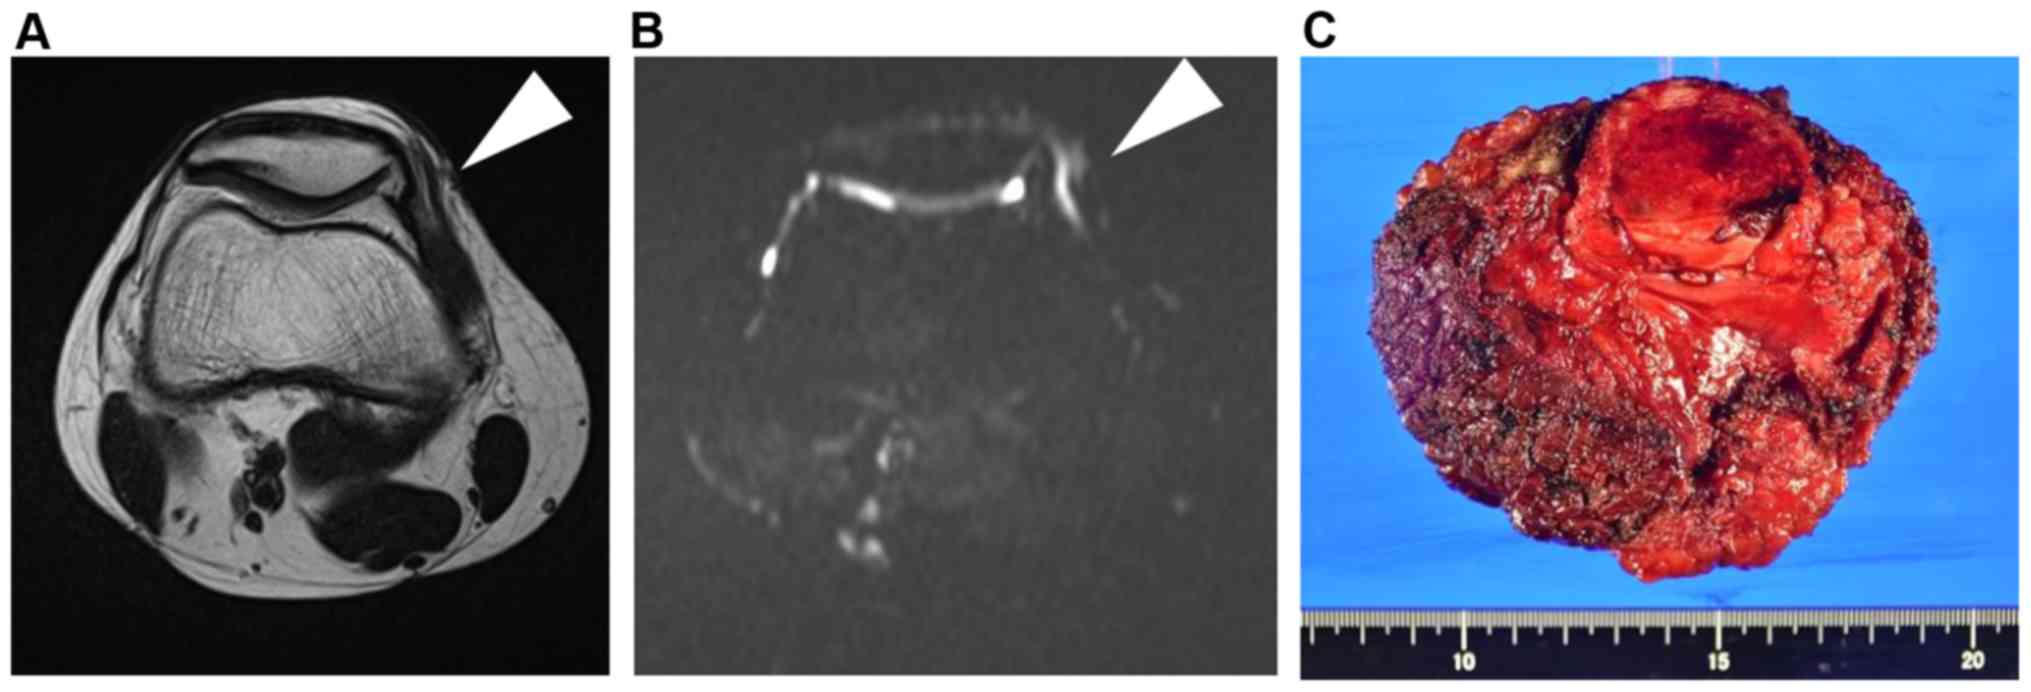

A 16-year-old man presented with pain and a mass on the medial side of his right knee for 1.5 years prior to when he visited his first doctor. The tumor was approximately 3 cm in diameter. He underwent magnetic resonance imaging (MRI) that revealed a circumscribed soft tissue tumor located in the subcutaneous tissue. The tumor had an iso-signal intensity on T1-weighted sequences and high signal intensity on T2-weighted sequences (Fig. 1). The doctor diagnosed the tumor as benign and then performed a marginal resection. However, postoperative histological diagnosis revealed spindle cell sarcoma. The patient was then referred to our hospital for a more specialized treatment. We identified dense freckles and café-au-lait spots on his right inguinal region to the knee (Fig. 2). He had no family history of NF1. The segmental freckles led us to suspect MPNST associated with mosaic localized NF1. Preoperative MRI before additional wide resection showed that a residual tumor appeared to exist adjacent to the patella (Fig. 3A and B). We then confirmed the absence of metastasis and conducted an additional wide resection where part of the vastus medialis, the medial patellar retinaculum and joint capsule, and the patella were resected with the residual tumor. Soft tissue defect was reconstructed with pedicled anterolateral thigh musculocutaneous flap. There was no evidence of residual tumor and surgical margin proved to be negative (R0 resection) (Fig. 3C). The patient did not present with local recurrence and distant metastasis 1.5 years after surgery.

Figure 1.

Coronal and axial images obtained during the first round of preoperative magnetic resonance imaging. (A) coronal T1-weighted, (B) coronal T2-weighted and (C) axial T2-weighted images are presented. White arrowheads indicate the tumor.